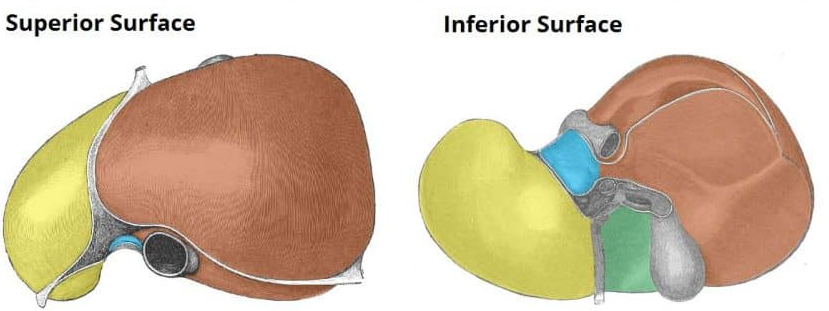

Right liver lobe

orange highlight

Left liver lobe

yellow highlight

Falciform ligament

Coronary ligament

Round ligament

Caudate lobe

blue highlight

Quadrate lobe

green highlight

Porta hepatis

What do all these make up (this is the posterior liver)

Inferior vena cava

Hepatic artery

Hepatic portal vein